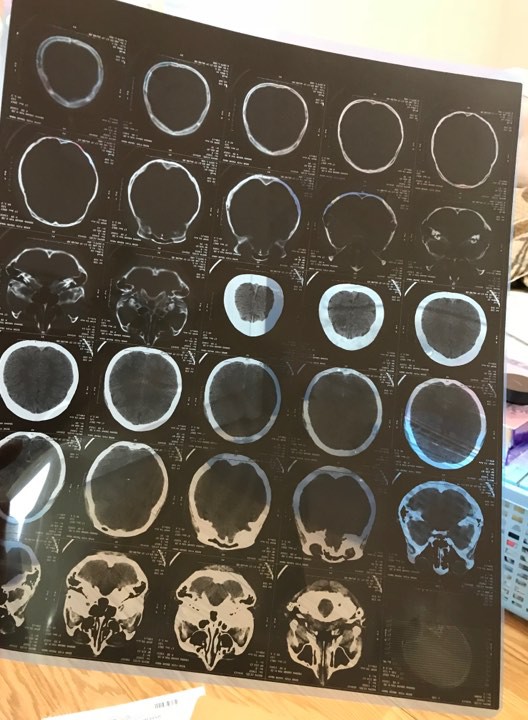

Giấy tờ khi chị V. bị đánh phải nhập viện cấp cứu. Ảnh:NVCC